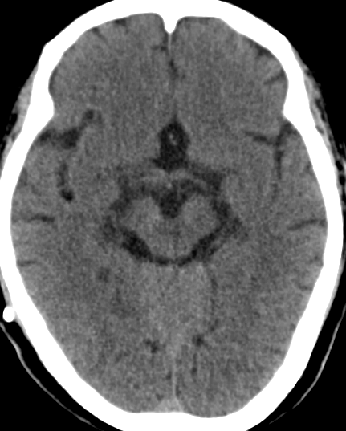

2013-8-12 CT

2013-8-13 调压130——150,头痛症状无明显好转